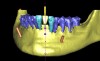

Following the first goal of orthodontia—moving tooth No. 22 to a proper functional and anatomical position—a periodontal reevaluation was performed, demonstrating an improvement in short- and long-term tooth prognosis. At this time, the decision was made to abort continual extrusion of teeth Nos. 21 and 22, although some attachment level discrepancy remained between Nos. 21 and 22 (Figure 14). Implant diagnostics ensued and included mounted study models and a diagnostic wax-up. A scanning appliance was created to demonstrate the desired prosthetic outcome requirements, and the patient was referred for computed tomography (CT) scans. CT scan assessment demonstrated successful orthodontically directed GBR to allow implant placement (Figure 15 and Figure 16). Only minor GBR therapy would be needed and could be accomplished simultaneously with implant installation. Guided implant placement occurred, using an open flap approach (Figure 17). During surgery, root dehiscences were noted on teeth Nos. 21, 22, 24, and 25, as well as the anticipated dehiscence following implant placement at No. 23 (Figure 18). A positioning reference (index) was secured after implant placement to facilitate a provisional prosthesis at stage II surgery. Cortical perforations then were placed adjacent to the implant to encourage angiogenesis (Figure 18), and mineralized freeze-dried bone allograft enhanced with platelet-derived growth factor was placed over the dehiscences for purposes of guided tissue regeneration and GBR (Figure 19). A highly resorbable collagen membrane was placed to stabilize the allograft. The flap was coronally repositioned, and primary-intention wound healing was achieved (Figure 20 and Figure 21). Following 4 months of stage I surgery, implant uncovery and immediate provisionalization were performed in conjunction with connective tissue grafting. Final orthodontic tooth movement then ensued, using the implant as anchorage to optimize end-tooth movements, interroot separation, and the cuspid-protected occlusal scheme. A final impression then was secured, and a zirconia abutment (Figure 22) with an all-ceramic restoration was fabricated for the prosthetic phase completion of No. 23 (Figure 23 through Figure 25).